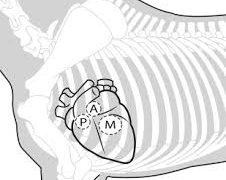

犬の心臓弁膜の疾患(acquired heart diseases)家畜の後天性心疾患については、各種動物でかなりの発生をみていますが、ここではその主なものについて記載します。犬の心臓弁膜の疾患(valvular heart disease...